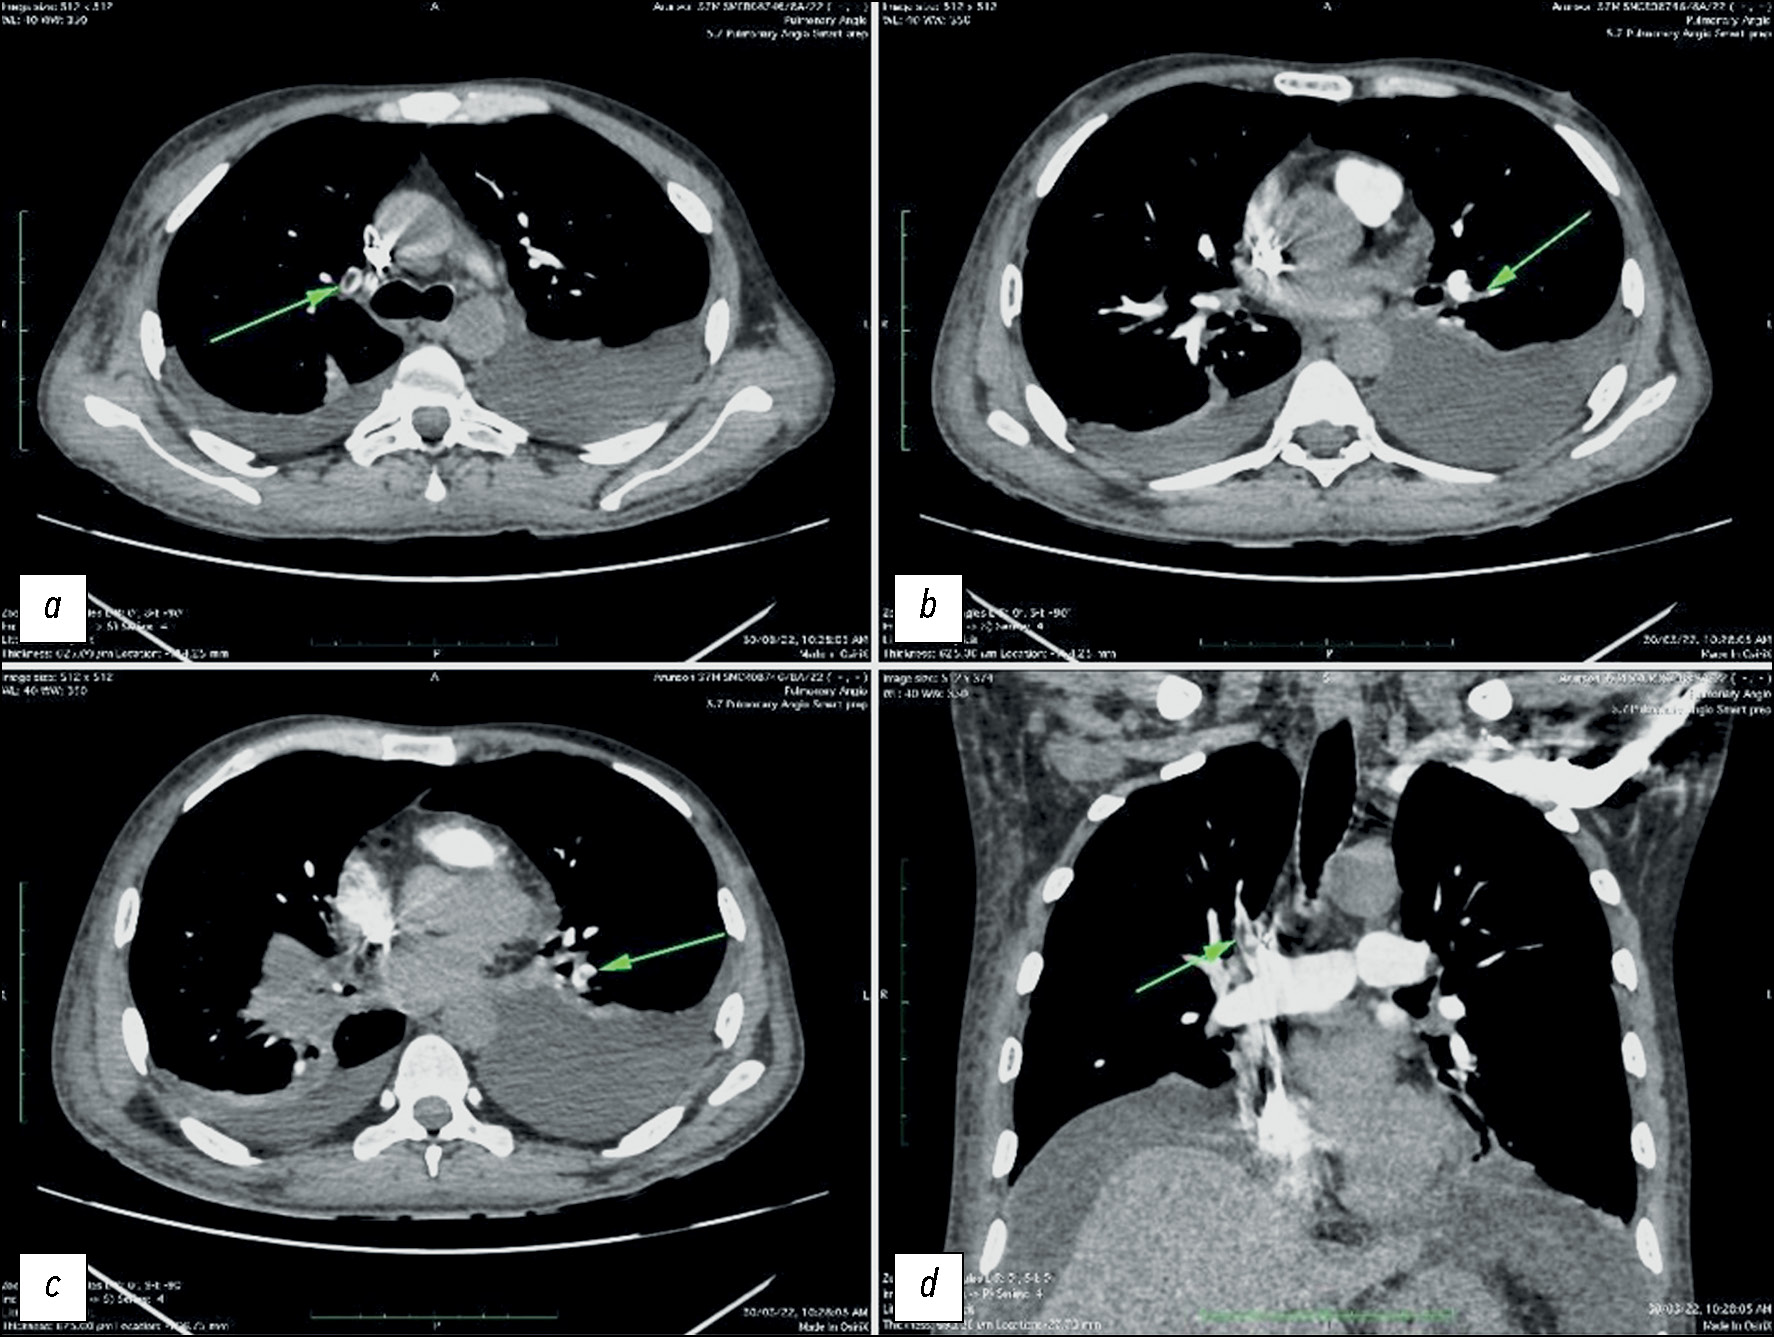

Несколько наглядных случаев изменений сосудов лёгких и кишечника у пациентов с COVID-19 показаны на рис. 1–3.

Рис. 1. Результаты компьютерной томографии, выполненной у пациента мужского пола, 27 лет, с COVID-19, у которого выявлен двусторонний плевральный выпот: a — тромб в лёгочной артерии непосредственно вблизи сегментарных ветвей; b — тромб в боковой сегментарной артерии нижней доли левого лёгкого; c — тромб в лёгочной артерии нижней доли левого лёгкого перед разделением на ветви; d — тромб в лёгочной артерии верхней доли правого лёгкого непосредственно проксимальнее сегментарных ветвей.